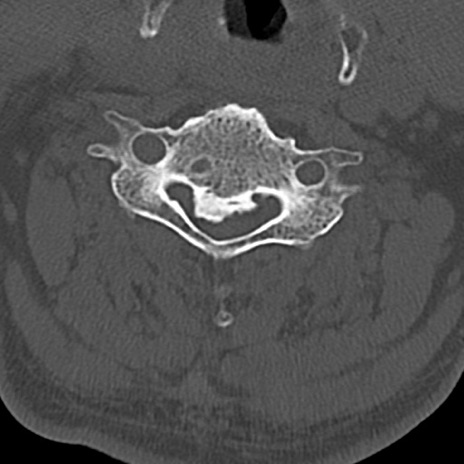

頚椎CT

横断像